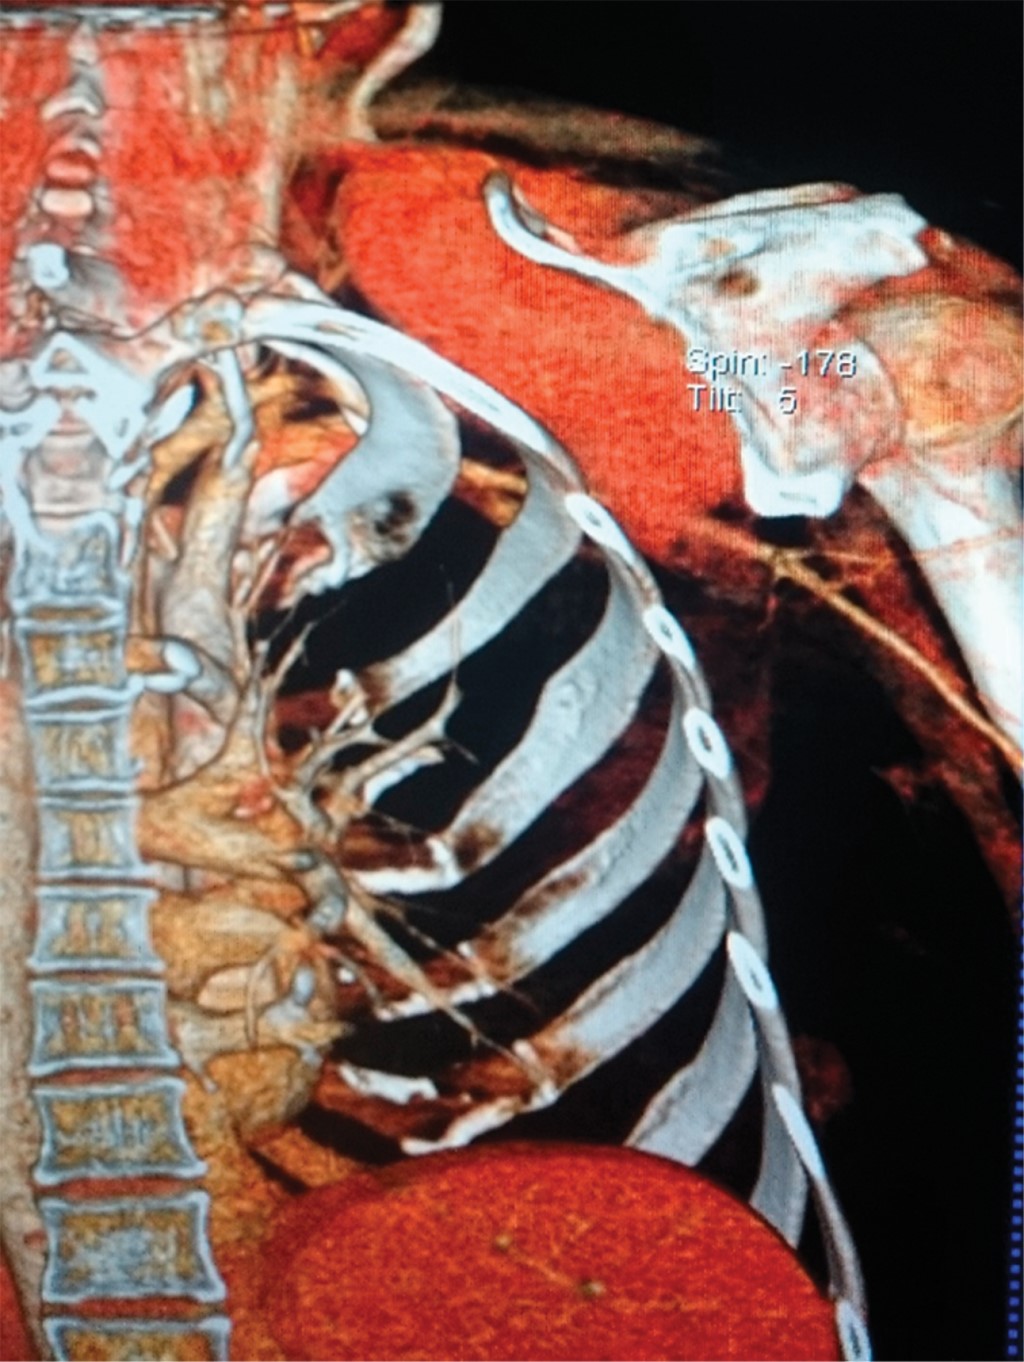

Por dolor postoperatorio se envió a la paciente a radioterapia, posterior a RMN, donde se encuentra lesión subescapular con extensión hacia la fosa supraclavicular, que involucra los músculos subescapulares. No se establece con certeza si es tumor graso o no, ni si tiene o no extensión intratorácica, por lo que se realiza tomografía computarizada que muestra un tumor subescapular derecho heterogéneo con tamaño de 11.6 × 11.5 × 9.4 cm, con aumento en su vascularidad, que comprime y desplaza la yugular interna, no erosiona la parrilla costal, erosiona la espina escapular, sin adenopatías, involucra el músculo subescapular y lo reemplaza en su totalidad (Figuras 1 y 2). Se observa paquete neurovascular axilar y supraclavicular respetado. Se hace biopsia percutánea en mayo de 2015 con RHP de miofibromatosis.

Figura 1

Figura 2